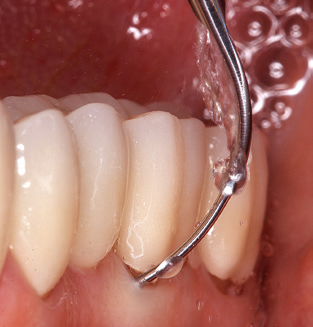

Of course, the use of instruments for mechanical removal of the biofilm is a central component of SPT and thus of primary significance. Consequently, the SPT workflow comprises both supragingival and subgingival cleaning. In our concept, a combination of hand instruments and machine cleaning has proven advantageous. A number of options are available for the mechanical procedures: sonic devices, ultrasonic devices and powder jet devices.

Although the fundamental principle of the ultrasonic devices remains, recent years have seen a whole host of further developments, resulting in an increase in efficiency, patient comfort and safety. These innovations are all present in the ultrasonic device (Tigon+, W&H Dentalwerk Bürmoos GmbH) currently employed by the authors, for example.

Good illumination of the working field facilitates the process considerably. The system used by the authors achieves this thanks to a 5x LED ring integrated in the handpiece. Naturally, a range of working tips for different indications is also offered. A straight, universally employable tip is the basic instrument required for machine cleaning of natural teeth (Fig. 5a and b). Curved tips, which allow access to exposed furcations, are also available for hard-to-reach areas in the posterior region (Fig. 6).

Fig. 4: Flexible probes with millimetre markings are recommended for the probing of dental implants (e.g. Colorvue Kit PCV11KIT6, Hu­Friedy). – Fig. 5a and b: A straight working tip (1P, W&H Dentalwerk Bürmoos GmbH) is a suitable instrument for use on all natural teeth. – Fig. 6: Curved working tips (3Pr/3Pl, W&H Dentalwerk Bürmoos GmbH) lend themselves to the processing of difficult-to-reach areas of the tooth and root surfaces (e.g. furcations). – Fig. 7: The tapered, hexagonal implant cleaning tip (1I, W&H Dentalwerk Bürmoos GmbH) permits atraumatic and efficient cleaning of the crown and abutment surfaces. – Fig. 8: Titanium and carbon curettes are suitable instruments for the manual cleaning of the implant surfaces.